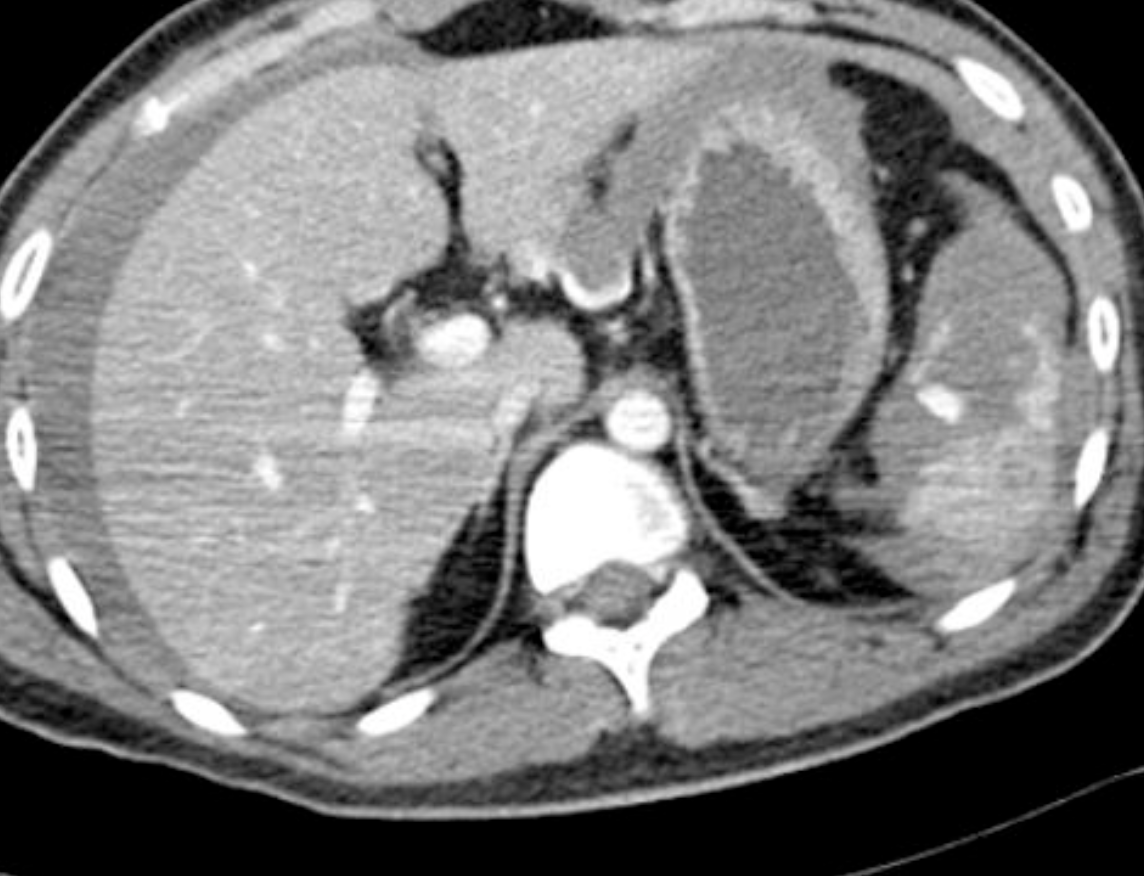

Extensive splenic lacerations extending to the hilum with areas of devascularisation. No evidence of active bleeding or pseudo-aneurysm. There is extensive haemoperitoneum throughout the abdominopelvic cavity. Cholecystectomy clips are noted along with extrahepatic and first order intrahepatic duct dilatation. Liver is uninjured. Adrenal glands, kidneys and pancreas are uninjured. Bowel is unremarkable. Lung bases are clear. No bony injury identified.

Conclusion:

AAST grade IV splenic injury with extensive haemoperitoneum.

Case Discussion

Further history obtained (after the CT) revealed a fall from 1.5 metres. Patient proceeded to successful splenic embolisation.